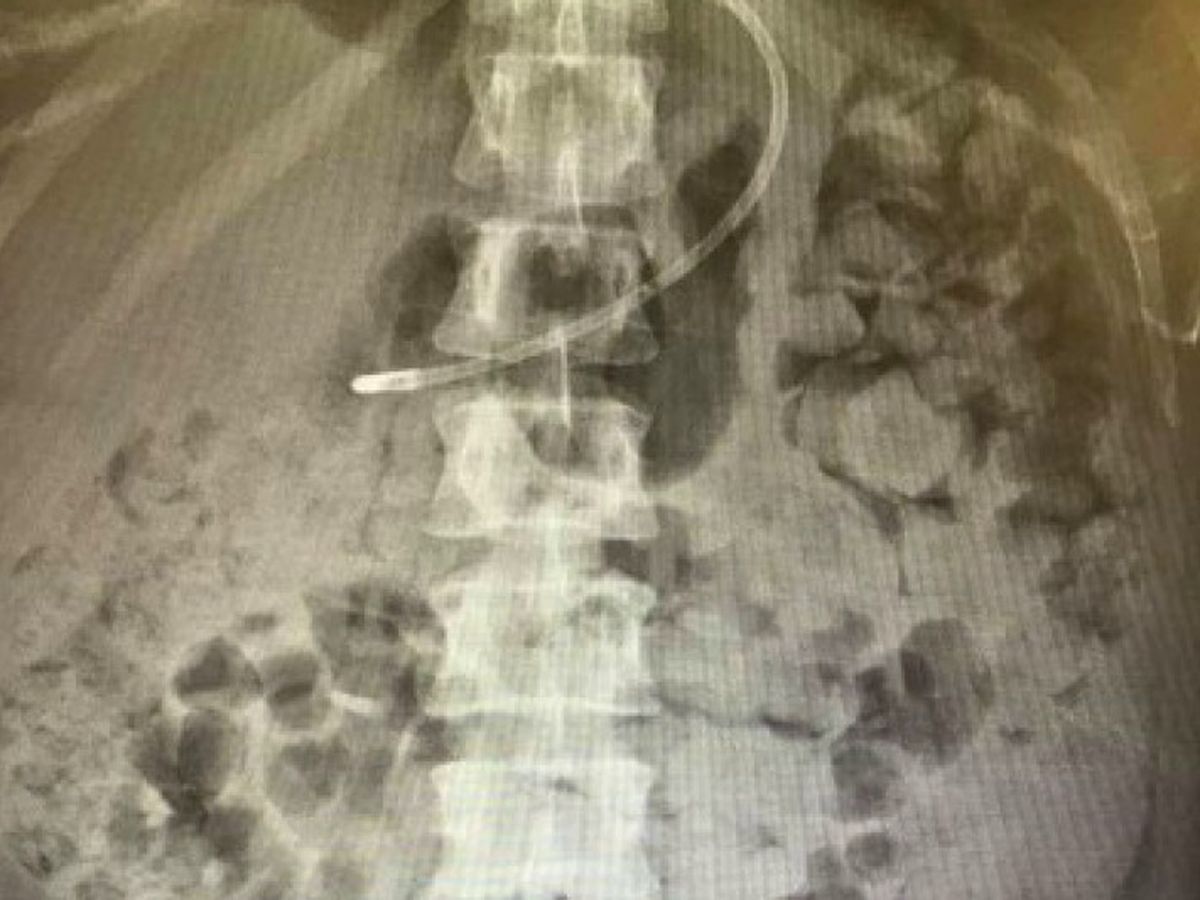

Can you imagine how it would feel to have your body so full of your own excrement that you were slowly suffocating? Yes, what you see is what you think it is…

Due to a slip of the scalpel, during a minor surgical procedure, Kelly Yeoman’s bowel was knocked, leaving her with a collection of infection which required two further surgeries to correct. As a result, her bowel is now unable to function, she is now horrifically fecally impacted (as you can see in the X-ray, her body is literally filling with poo), she is regularly vomiting a foul mixture of her last meal and her own excrement, and she is struggling to breathe. For ten long weeks, Kelly has been lying in her hospital bed, on a cocktail of the strongest painkillers, being subjected to a series of increasingly humiliating and painful procedures, while nobody seems able to find a solution. At any moment, her bowel could perforate, which (if she is lucky enough to survive the complications) will result in a colostomy bag for the rest of her life. She is allergic to many things including latex and oral antibiotics and has a number of health issues, all of which need to be carefully considered. Nothing seems to be working and we are watching her go gradually downhill – she is almost unrecognisable as our happy, strong and determined friend. Every day she seems to fade further away and we are all beginning to fear the worst.

The operation I had at St Michael's was to see if I also had endometriosis so they didn't miss anything and make sure I was having the correct treatment. Luckily I was clear of this which is a relief. From the day of this operation I did not go to the toilet and was taking laxatives with no effect. I then had an infection deep inside my stomach from the operation. while in hospital for treatment of the infection they did a CT scan which showed my bowel to be inflamed (stranded) and I was heavily constipated... I went home on medication to elevate this which didn't help. I carried on my active life, which I had done from the 6th day after my operation (riding and competing) fast forward a couple of weeks and I found myself back in hospital (after much argument may I add, from my GP and a close friend who literally dragged me there) the infection hadn't cleared (which is actually very common with collection pockets of infection from surgery so I was told by the surgeon!) so I ended up having another surgery to treat this which went well! They also tried to treat the constipation and it literally would not work.. they then found with more investigation that my bowel was in fact not moving, hence why I was constipated previously which then turned to fecal impaction and then I was told it was because it had been knocked in surgery, which made sense due to the infection as well! A while later they did another X-ray which my team gave to me so I could see the extent of what I was dealing with, which I posted on my own Facebook wall and explained this is what I was dealing with.

It was also said that the X-ray was of my chest (the only comment about my chest was my original post with my X-ray saying "and yes it's up in my chest too" where I was referring to the fact that I was so impacted everything was being pushed upwards against my diaphragm. NOWHERE did it say it was an X-ray of my chest...